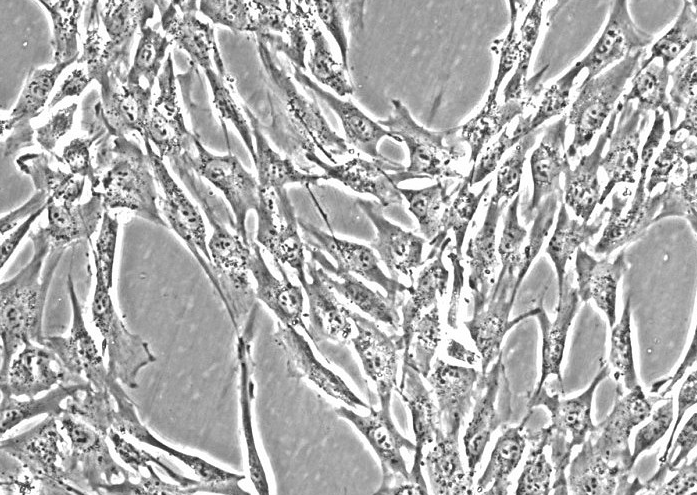

悬浮细胞

- 细胞形态:

淋巴母细胞样